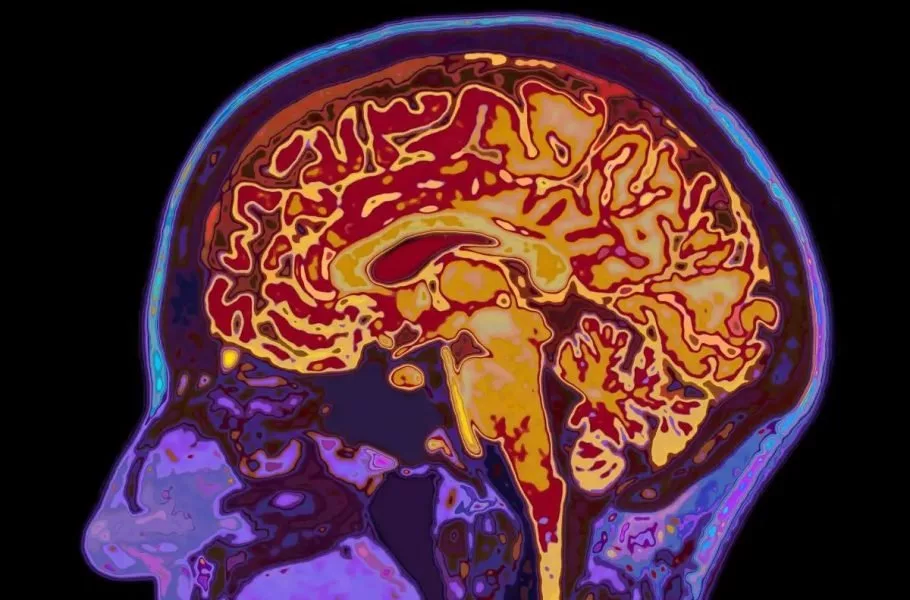

شاید فکر کنید با تمامشدن دوران نوجوانی، مغز شما هم به بلوغ و رشد نهایی رسیده است. اما دانشمندان دانشگاه کمبریج این باور قدیمی را رد کردهاند. آنها با اسکن مغز ۴ هزار نفر (از نوزاد تا ۹۰ ساله) کشف کردند که مغز انسان نه یک مسیر خطی، بلکه ۵ دوران متمایز را طی میکند. محققان میگویند مغز ما تازه در اوایل دهه ۳۰ زندگی وارد فاز بزرگسالی میشود.

تصور رایج این است که نوجوانی در ۱۸ یا ۱۹ سالگی تمام میشود، بااینحال مطالعه جدید نشان میدهد که مغز تا حدود ۳۲ سالگی همچنان در فاز «نوجوانی» باقی میماند. در این دوران طولانی (از ۹ تا ۳۲ سالگی) مغز مشغول سیمکشی مجدد و افزایش بهرهوری است. این همان زمانی است که بیشترین خطر بروز اختلالات سلامت روان وجود دارد، زیرا مغز درحال تغییرات بنیادین است.